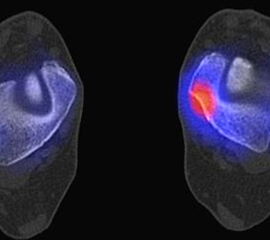

Die Abbildungen 4.2.a bis d zeigen den typischen Aspekt einer talacalcanearen Coalitio. Es besteht nur eine linksseitige, symptomatische Coalitio talocalcaneare (4.2.a und c); das 35 Tage zuvor angefertigte MRT zeigt keine auffälligen Signalveränderungen (4.2.b und d).